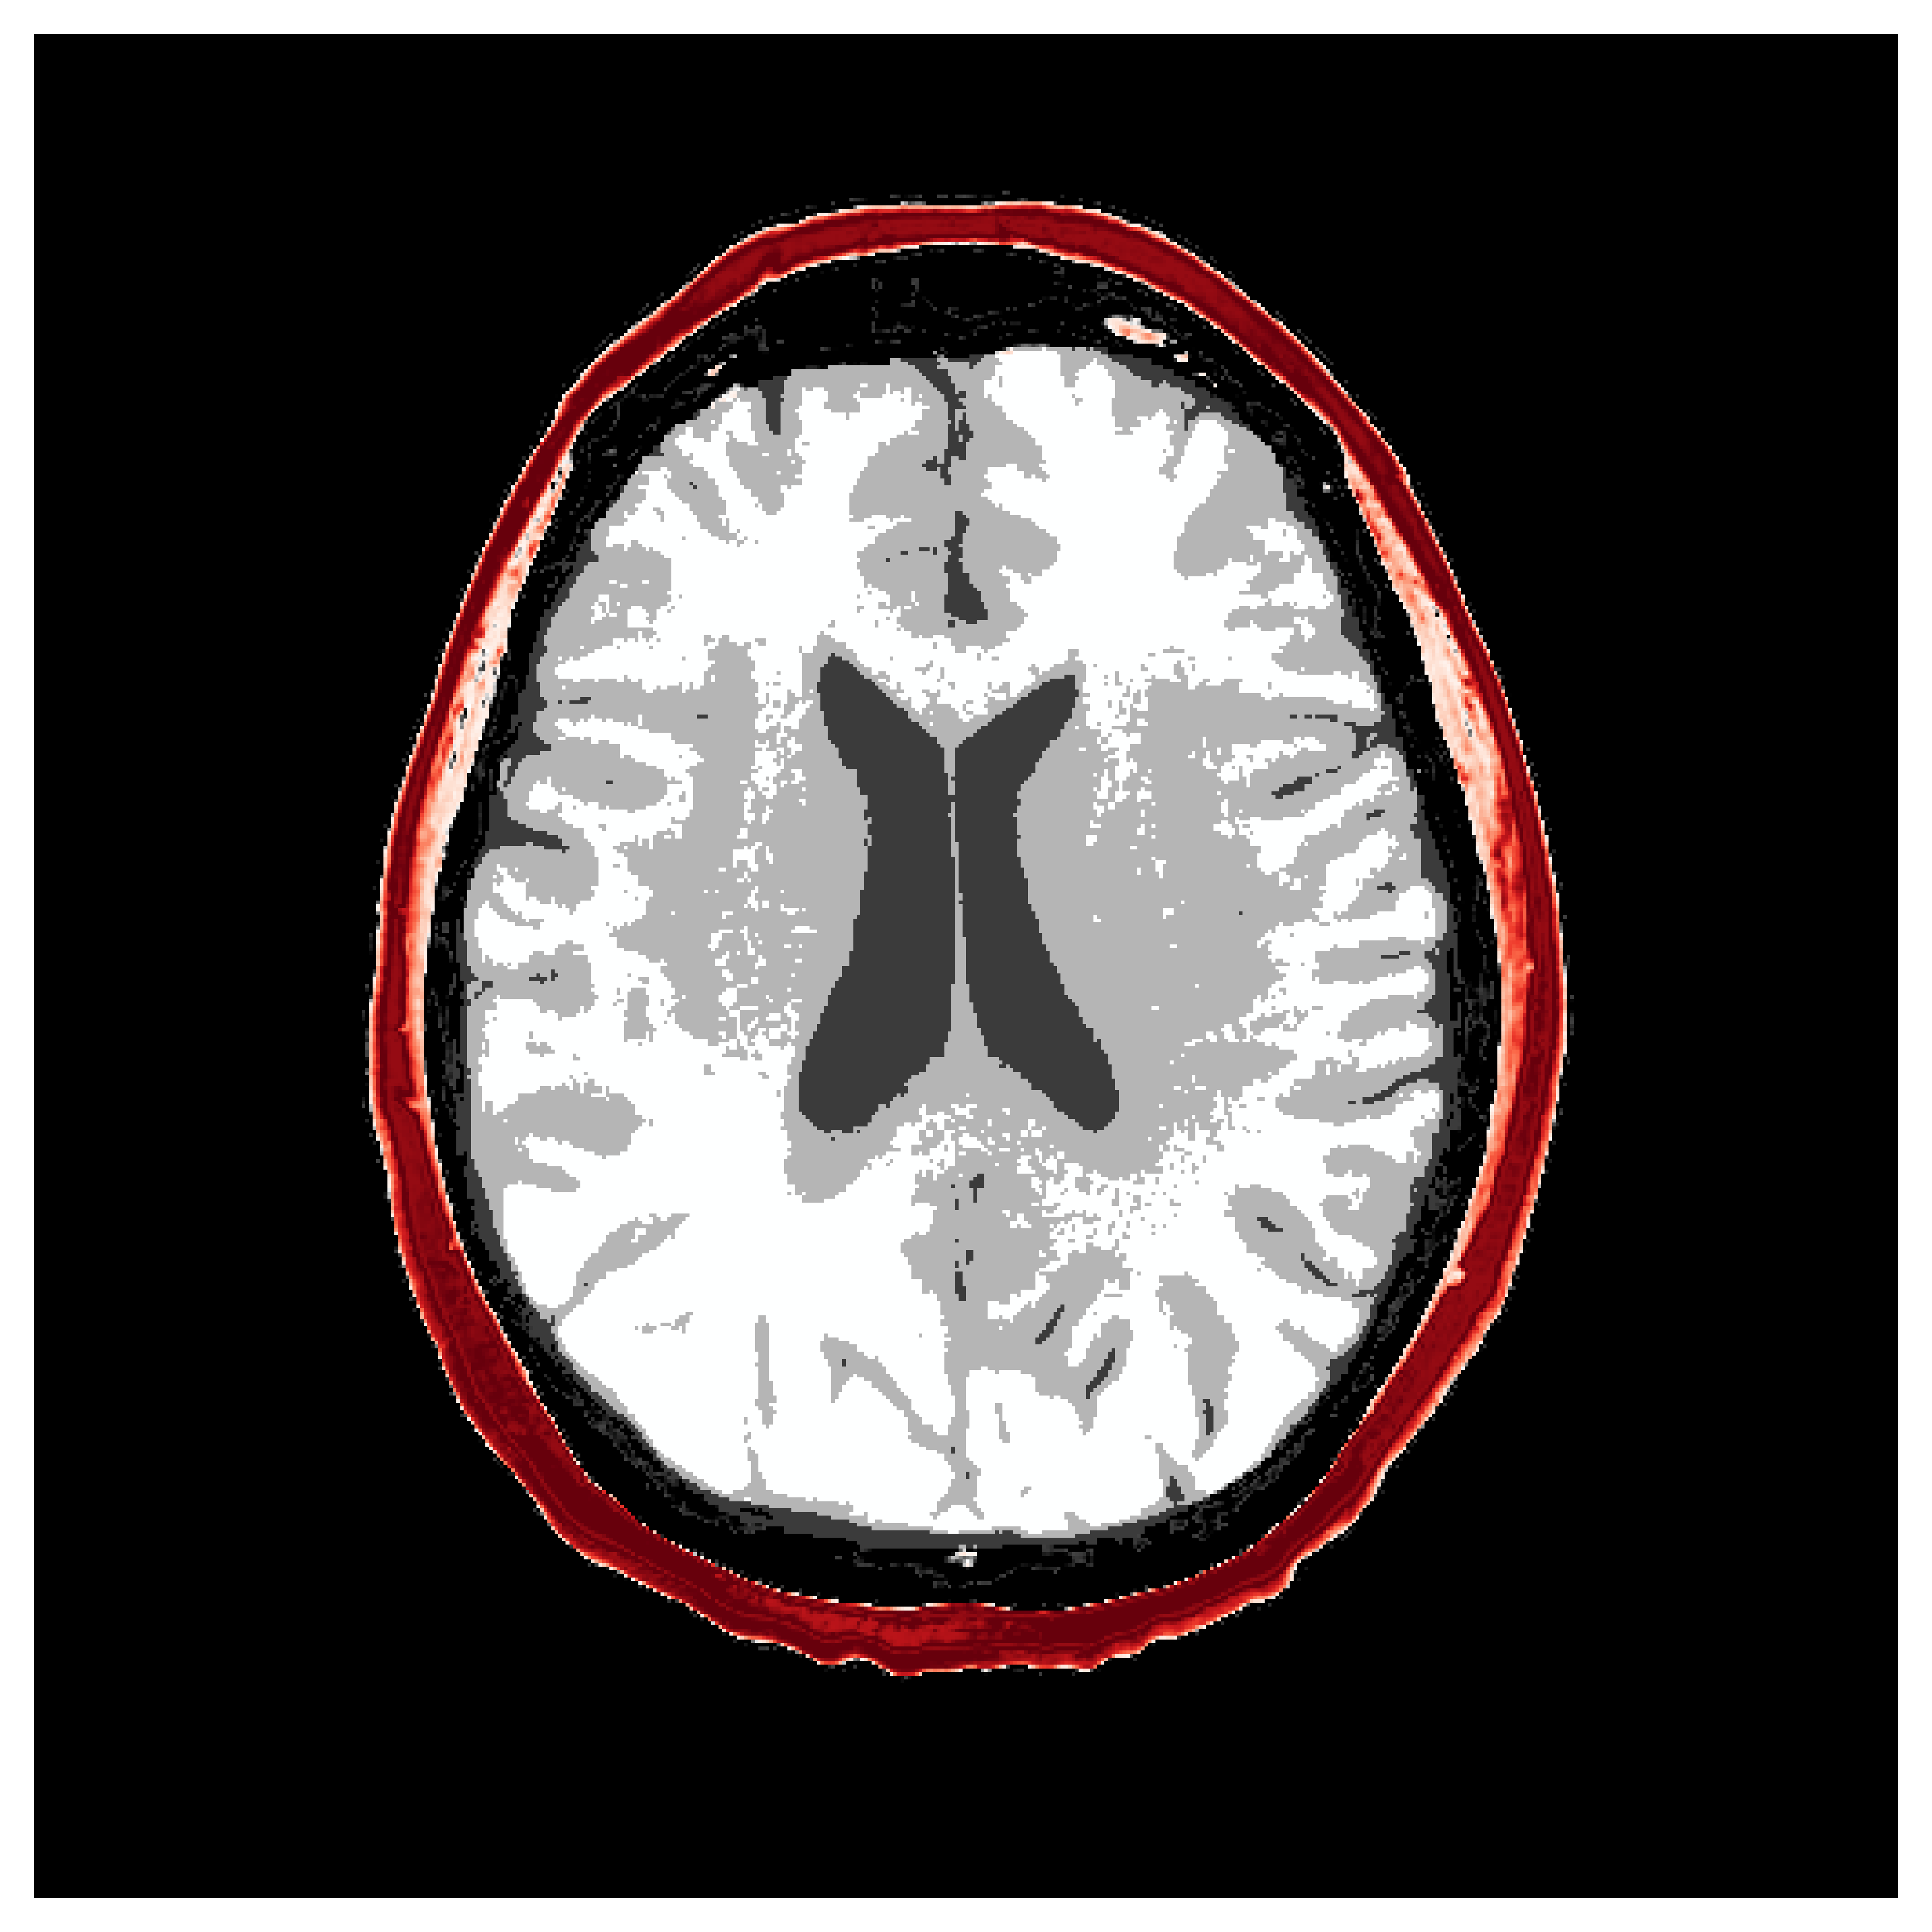

The first step of implementing ASPIRE concerns obtaining samples from a realistic prior for the target parameter vector , in this case, gridded velocity parameters of human brains and skulls. The parameters collected in the MIDA dataset [56] correspond to a single 3D volume for the acoustic velocity collected from a single subject and will unfortunately not be appropriate to train a neural model that will generalize to other human patients. As far as we know, there is no dataset that includes acoustic velocity collected from many patients, so we made our own dataset based off the multi-subject FASTMRI dataset [57]. This custom dataset, detailed in Section \thechapter.A, comprises N=1000 diverse acoustic velocity parameters collected from different human patients, . This size of datasets facilitates generalization of the amortized posterior sampler across different datasets collected from unseen patients. The dataset is accessible via the repo ASPIRE.jl.

Appendix \thechapter.A FASTMRI acoustic dataset creation

Based off of the MRI dataset [57], we manually assigned acoustic values to MRI intensities by following the table of acoustic brain tissue properties in the supplemental section of [47]. Although MRI intensities are not necessarily related to acoustic tissue properties, we found that we could produce reasonably realistic acoustic parameters as compared to the acoustic parameters from the MIDA volume. In Figure 19, we show some example training acoustic parameters. We also plot the average and standard variation between all 1000 training samples in Figure 20. From these plots, we note that there are few similarities between training examples apart from the biologically consistent human brain structures.